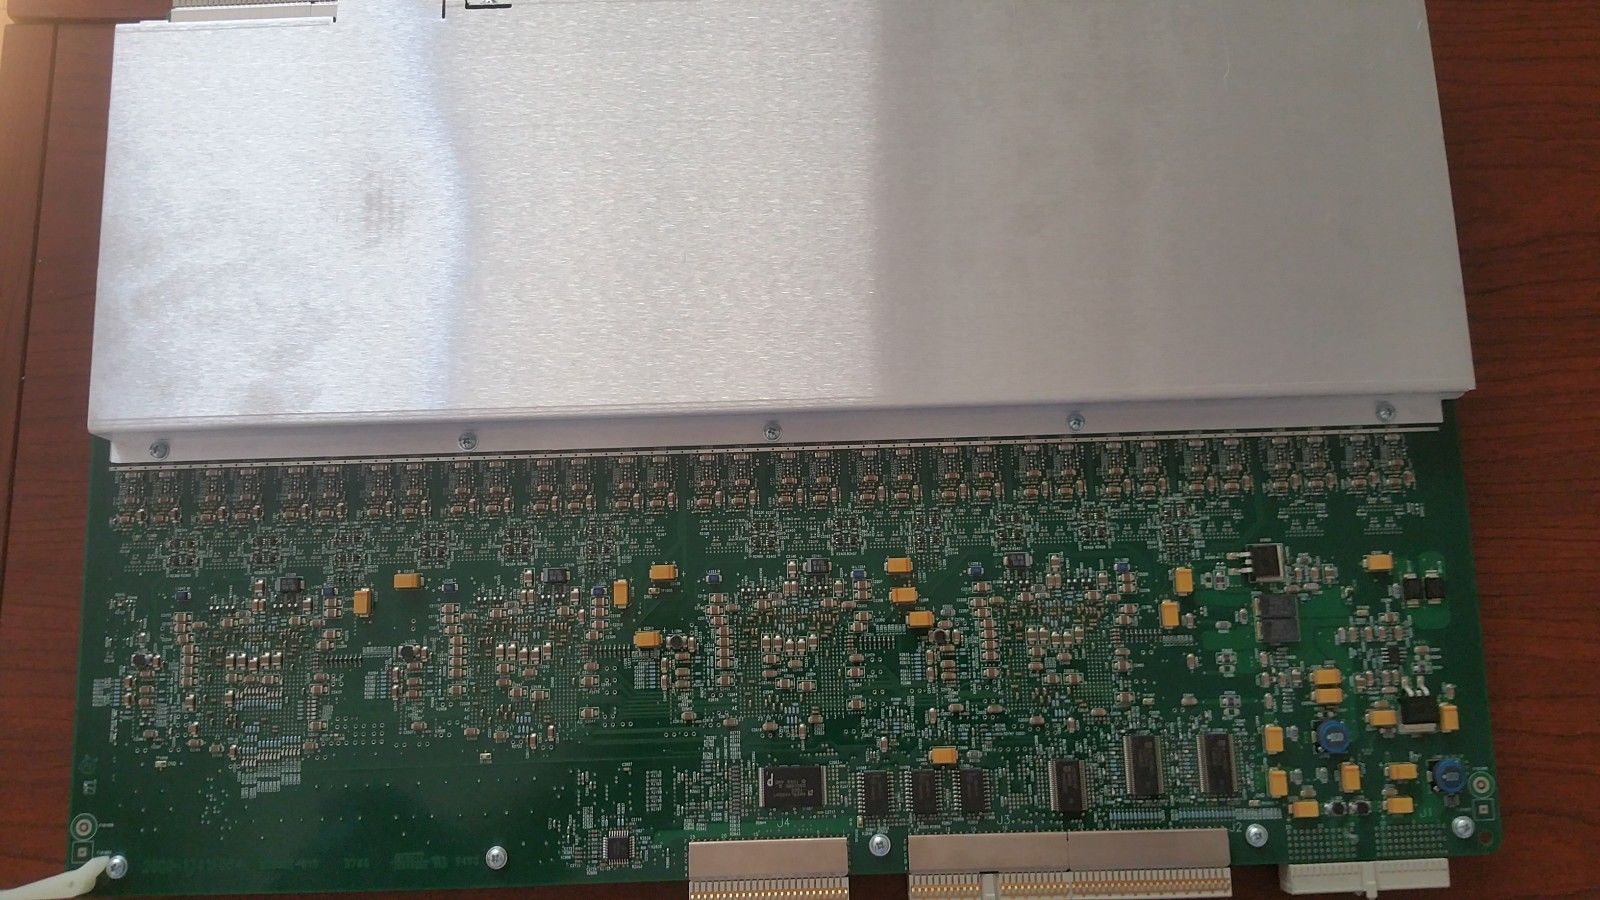

Philips-IE33-Ultrasound-PCB-Assy-Channel-Board

Sale price$ 3,831.02